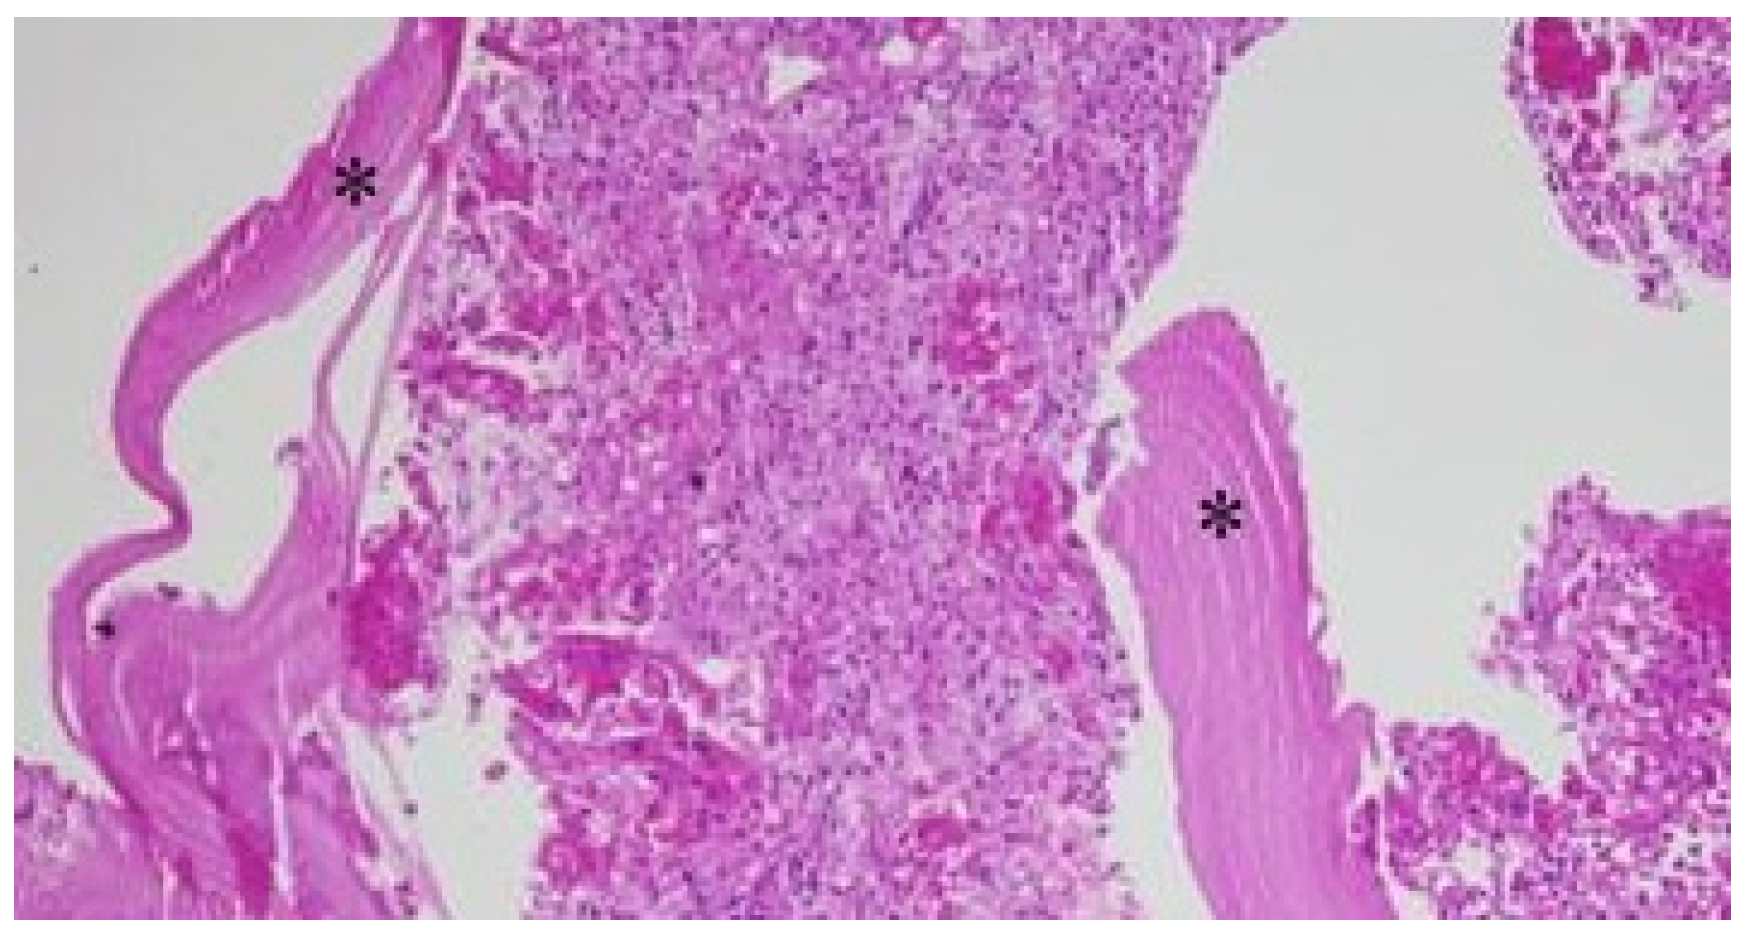

Case